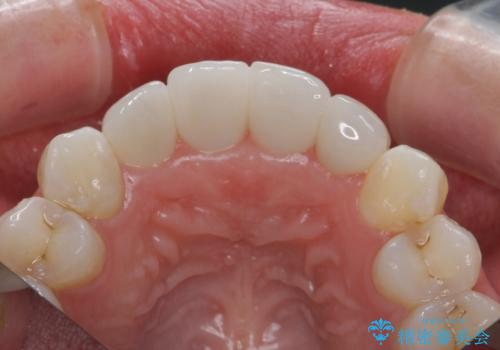

仮歯のまま放置していた前歯をセラミックに

- 仮歯のまま放置してしまい、変色を改善しきれいなセラミッククラウンをいれたい、と希望され来院されました。

特に虫歯の再発や神経の症状等問題を認めなかったので、審美的に優れるセラミッククラウンに仮歯を置き換えていきます。

- 52.8万円(ジルコニアクラウン×4・仮歯×4)費用は治療当時の料金となります

セラミッククラウンは長期的に変色しづらく、汚れのつきにくい審美製を長期的に保つことのできる治療方法です。